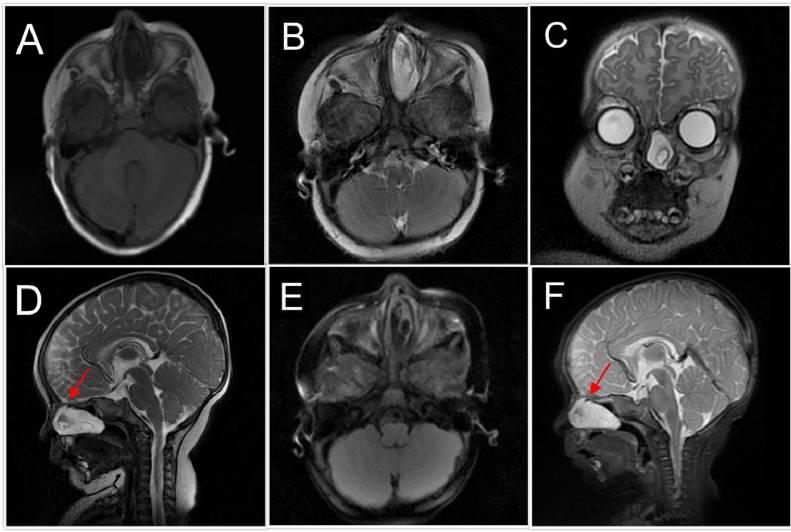

患儿4月龄,因鼻塞和吞咽困难就诊,体检和实验室数据正常。内窥镜检查发现一个占据整个左鼻腔的肿块。进行磁共振成像(MRI)以进一步明确病变。在MRI上,肿块表现出特定的信号特征。在T2加权图像上,病变呈均匀高信号,信号强度与脑脊液(CSF)相似(图1)。在T1加权图像上,病变相对于脑实质呈低信号(图1)。重要的是,在液体衰减反转恢复(FLAIR)图像上,病变显示出完全的信号抑制,与CSF含量一致(图1)。肿块边界清晰,边缘光滑,呈圆形至卵圆形。观察到一条信号强度相似的线性组织束,从病变处延伸到前颅底盲孔的一个小缺陷。对比后T1加权图像显示病变内没有增强(图2),这有助于将病变与潜在的增强炎症或肿瘤区分开来。盲孔处存在颅底缺损,再加上MRI信号特征,强考虑为左额脑膜脑膨出(图2)。

图1 MRI成像:(A)轴向T1,(B)轴向T2,(C)冠状T2,(D)矢状T2,(E)轴向FLAIR,(F)矢状STIR图像显示左鼻腔病变,T1信号低,T2和STIR信号高,FLAIR信号抑制。箭头表示颅底前方的一个小孔(盲孔)